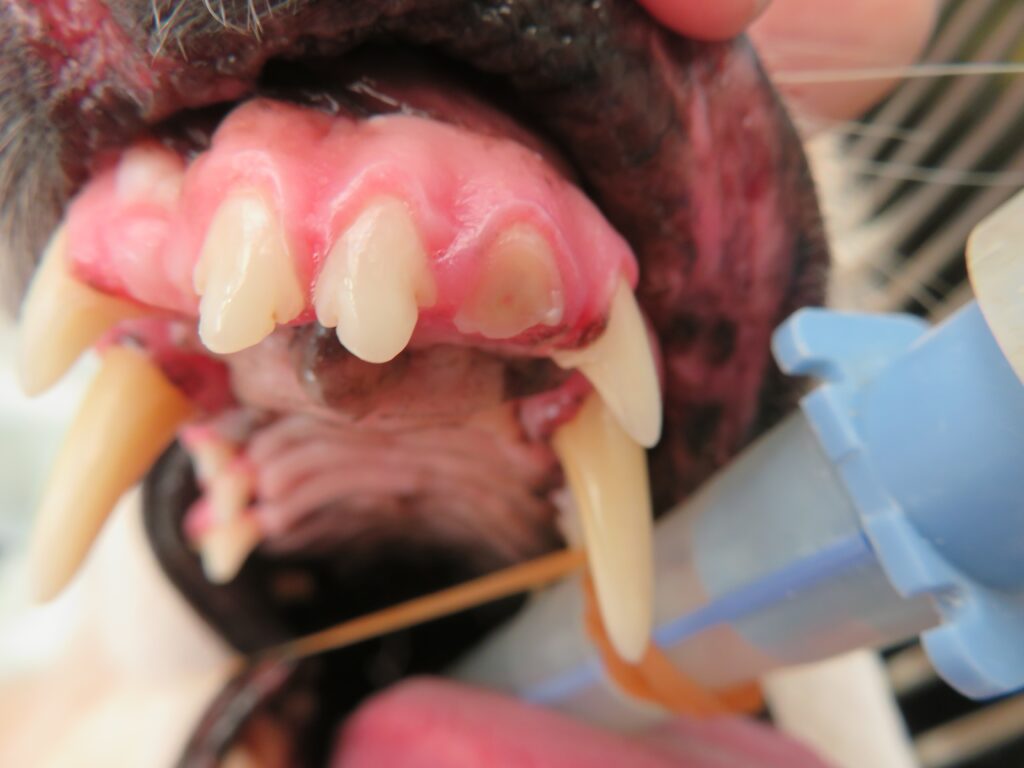

特に犬の場合、上あごの奥の大きな歯(上顎第四前臼歯)の破折が非常に多く、写真のように歯髄(いわゆる歯の神経)が露出して赤くみえることがあります。この状態を露髄といい、これを放置すると、最近が露髄した部分から入り込み、歯髄炎から歯髄壊死に至り、その後、歯の根っこの強い炎症(根尖周囲病巣)、さらには外歯瘻、内歯瘻に進行することがあります。